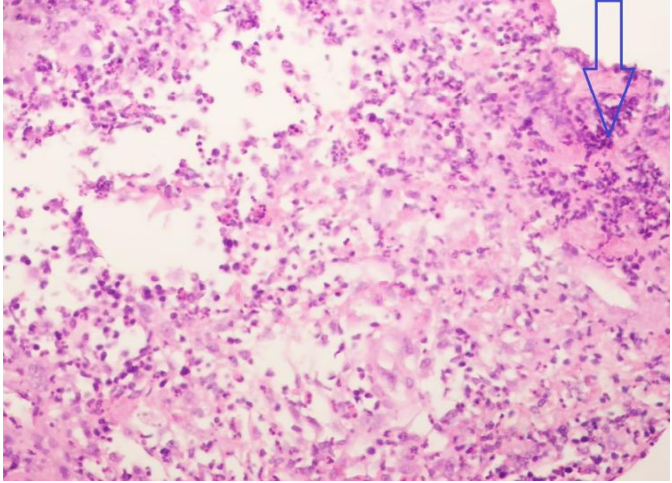

The patient was at first referred to hospital eleven years ago with these symptoms and had been drained and given antibiotics with diagnosis of breast abscess. Since then, four more times found with same symptoms and treated the same.  Never touched the crisp and underneath the biopsy at the same time.  Cystic fluid from his breast was aspirated, and the bacterial culture test showed no growth of any microorganisms after 48 hours. The cytology revealed predominantly neutrophils and degenerating cells in a hemorrhagic background, which suggested an acute suppurative inflammatory process of the affected breast as shown in Figure 2.

Figure 2. Histopathological findings of acute mastitis demonstrating areas of acute inflammation. Polymorphonuclear cells seen in acute inflammation are depicted by an unfilled blue arrow.